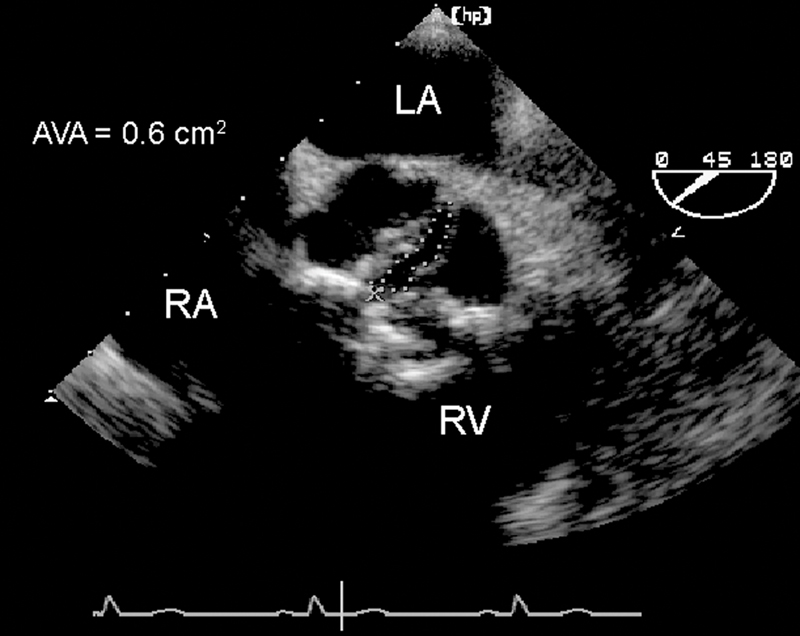

فحوصات تشخيصية لبعض امراض القلب والشرايين التاجية